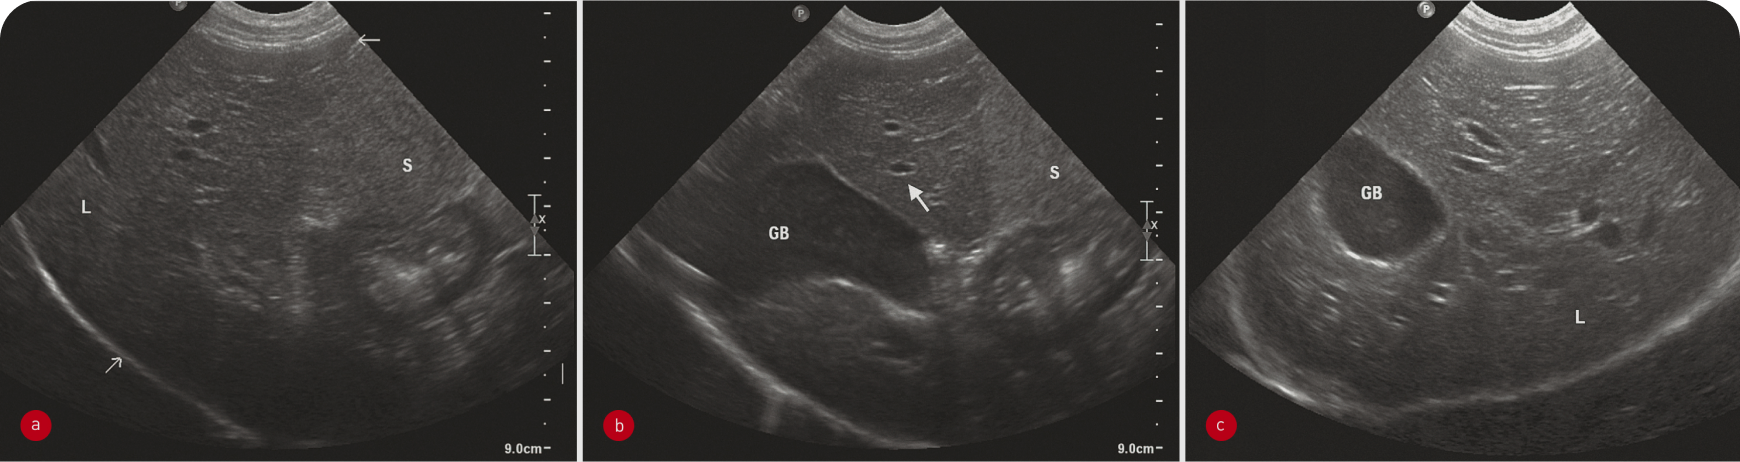

Паренхима печени однородная, слегка зернистой эхотекстуры, гипоэхогенна относительно серповидной жировой подушки и селезенки (Рисунок 3) и изо- или гипоэхогенна относительно правой почки (1). Контуры печени должны быть гладкими и ровными, очерченными тонкой гиперэхогенной капсулой. Разделение долей печени должно быть четким, если только в брюшной полости нет свободной жидкости. Печеночные вены легко визуализируются в паренхиме печени в виде трубчатых анэхогенных структур, а ветви воротной вены отличаются от системных вен гиперэхогенными стенками. Кроме того, по степени видимости портальных сосудов можно оценивать эхогенность ткани печени.

Как и на рентгенограмме, размер печени оценивают субъективно – по каудовентральному краю, который не должен выходить за пределы дна желудка. Правые доли проецируются более дорсально, часто лучше оценивать их в каудальном межреберном окне в 10-м или 11-м правом межреберье. В этом окне также удобно оценивать желчный пузырь, который обычно содержит анэхогенную жидкость и имеет очень тонкую гиперэхогенную стенку. У большинства собак среднего возраста в желчном пузыре выявляется подвижный эхо-материал. У кошек такое содержимое встречается довольно редко и требует дополнительного исследования функции желчевыводящих путей. Внутрипеченочные желчные протоки в норме не видны.

В основном при ультразвуковом исследовании можно выявить изменение размеров (чаще всего гепатомегалию) и эхогенности печени или наличие в ней узелка или объемного новообразования. Ультразвуковое исследование позволяет с высокой чувствительностью обнаруживать изменения паренхимы, но оно неспецифично, поэтому любые изменения следует интерпретировать с учетом клинических проявлений. Например, гиперэхогенную гепатомегалию на фоне желтухи у кошек можно с высокой вероятностью считать проявлением липидоза, а у собак с диабетом считать вариантом нормы. При этих двух заболеваниях паренхима печени также будет разрежена (Рисунок 4). Острый гепатит может характеризоваться гипоэхогенной гепатомегалией, а хронический – гетерогенностью тени и неровными краями печени.